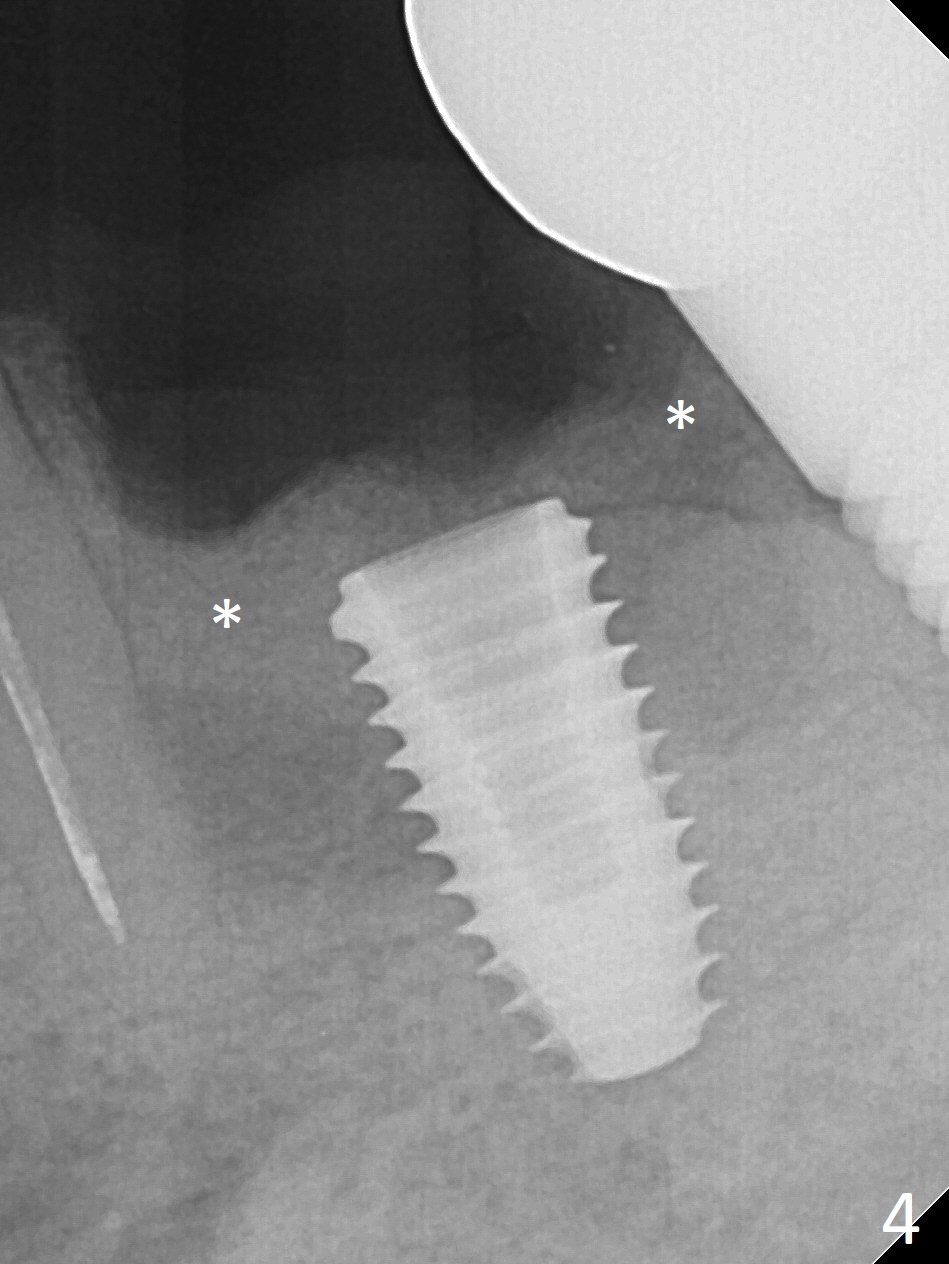

Extraction of the residual roots at #19 (Fig.1) is difficult, partially due to the hard one. The latter contributes to primary stability of 5x10 mm IS implant placed in the septum (Fig.2 (*),3). After change of cementation abutment (5.2x4.5(2) mm (short for provisional)) to hexed temporary abutment (5.2x8(2) mm), Collagen plug and Vera Graft are placed in the remaining mesial and distal socket (Fig.4 *). The last PA is taken when the temporary abutment (Fig.6 (<: hexed portion)) and provisional (P) are removed for modification. Before the abutment/provisional complex returns, a 2nd round of graft is placed (Fig.5 *). After the complex is seated, a 3rd round of graft is placed buccally (Fig.7). The temporary abutment is retightened 2 months postop (Fig.8). The implant appears to be osteointegrated 3.5 months postop (Fig.9). The gingiva looks healthy with (Fig.10) and without the provisional (Fig.11,12). It appears that there is no or minimal buccal plate loss. After insertion of a 5.7 x3 mm 15 degree (B-type) angled abutment (Fig.13) and height adjustment, impression is taken. The provisional is reseated after impression. The mesial bony defect seems to have been repaired nearly 8 months postop, 3 months post cementation (Fig.14 *). The bone density increases mesially 11 months post cementation (Fig.15).